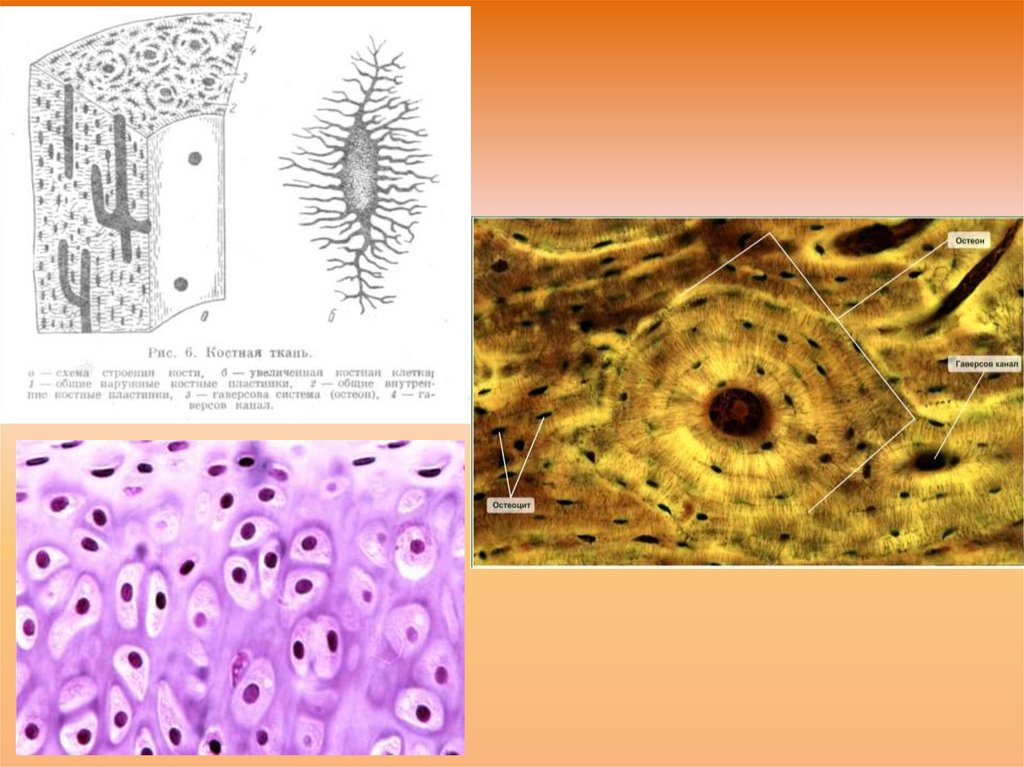

Структура грубоволокнистой костной ткани: наглядные примеры